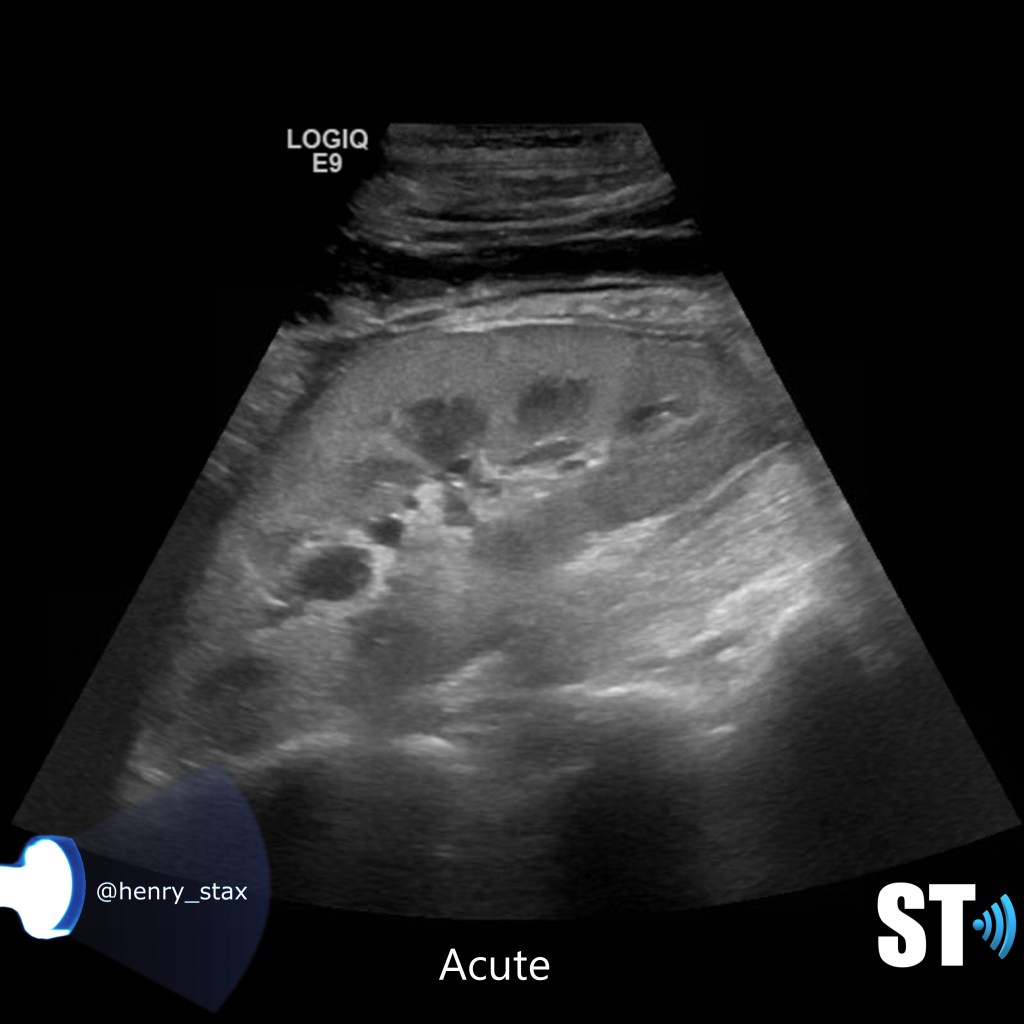

Acute pyelonephritis

Bacterial inflammatory disease of the kidney is commonly cause Eschericia coli. Most infections begin as UTI that ascends to the upper genitourinary system. the infection spreads from the renal pyramids into the renal cortex. The infection may be focal or diffuse. This condition usually presents with chills, fever, flank pain and laboratory findings of urinary infection.

Ultrasound may show an enlarged kidney with edema and increased echogenicity. You may also see a focal triangular area of altered echogenicity that displays reduced perfusion with color Doppler and power Doppler. If left untreated or inadequately treated that area can turn into an abscess.

For our purposes we need to tell whether the kidneys are hyperechoic or not, also is the corticomedullary (cmd) differentiation preserved or is it lost, this can give you clues as to the chronicity of renal parenchymal disease. If the cmd is easily seen it may suggest a more acute process, whereas chronic disease will usually show echogenic and atrophic kidney with little to no differentiation of the cortex to medulla